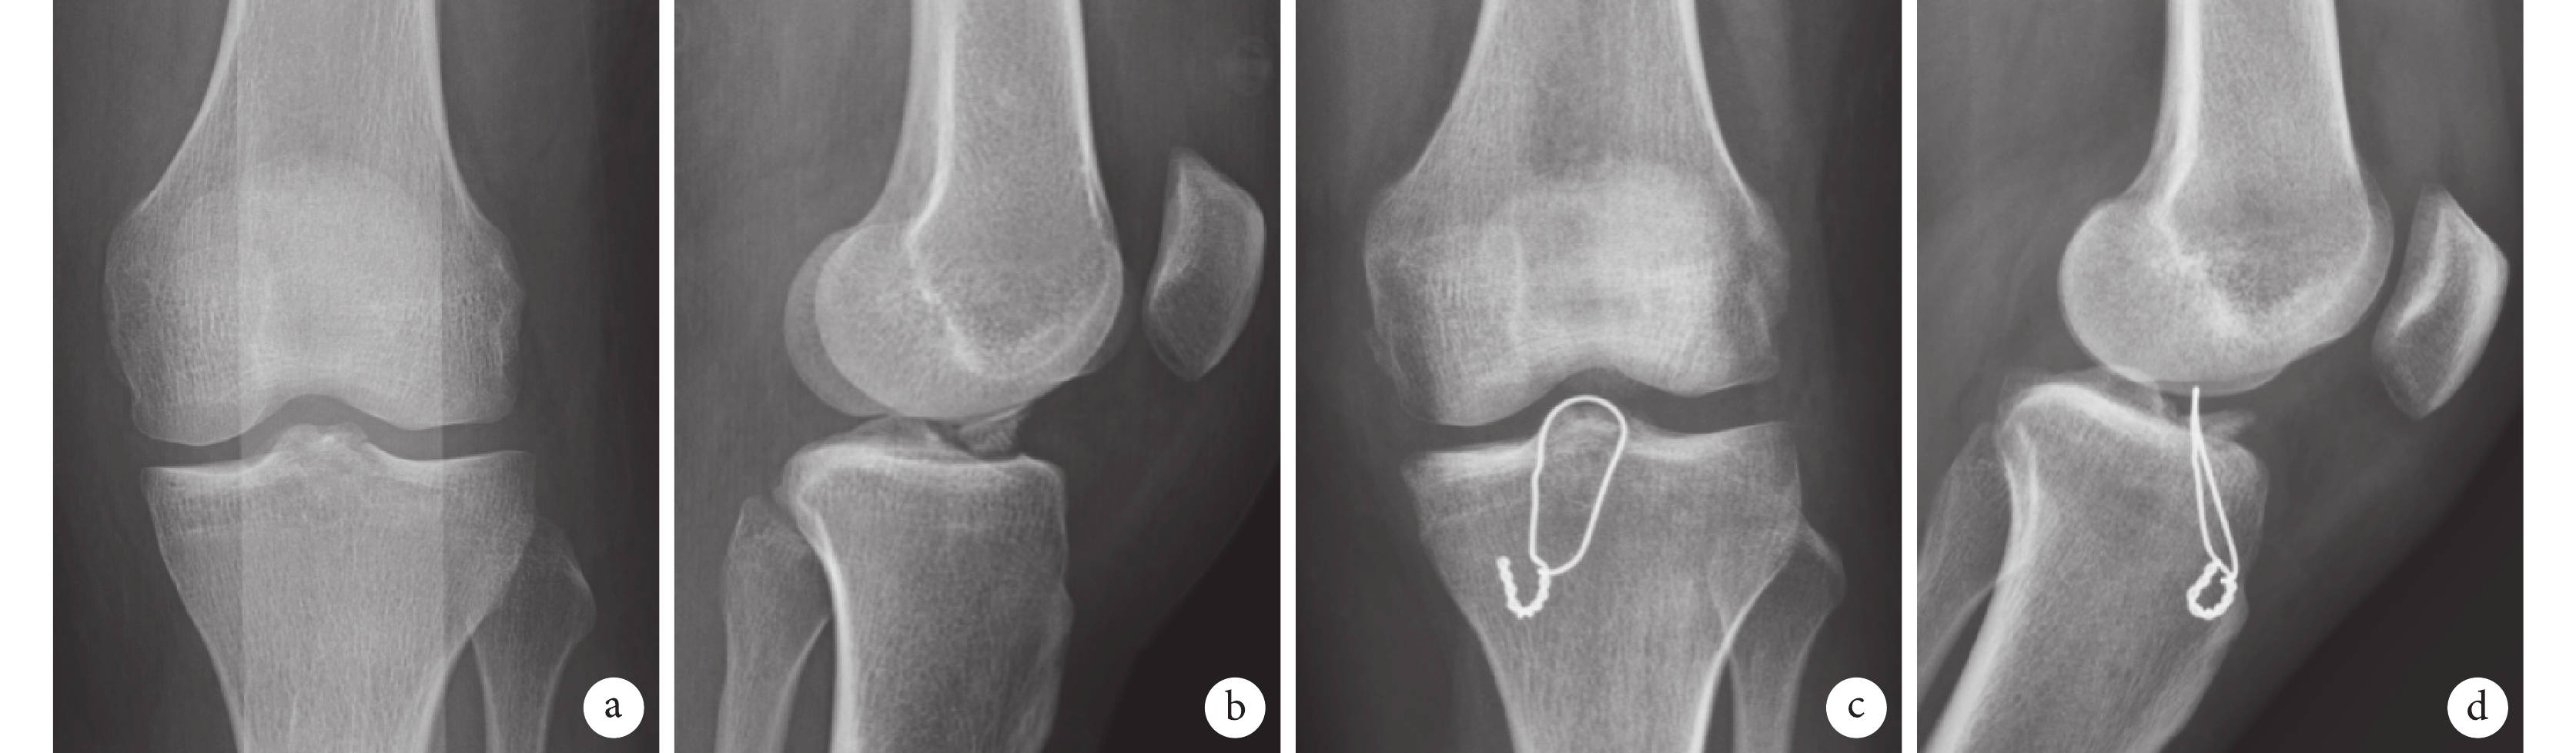

a、b. 術前正側位 X 線片,術中骨折塊再碎裂無法進一步調整固定位置,骨折塊前份部分上翹;c、d. 鋼絲固定術后 3 個月復查正側位 X 線片,骨折前份畸形愈合。患者,男,39 歲,ACL 止點撕脫骨折